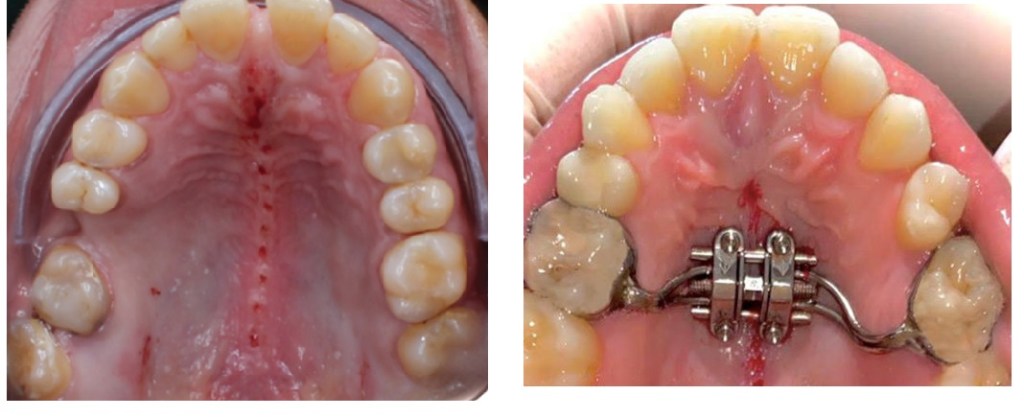

While literature on the procedure is missing, the common understanding is that EASE sits in between MARPE and SARPE. A transpalatal distractor (TPD) with footplates stabilized with a screw is placed in the palate and the expansion is facilitated by achieving pterygomaxillary separation with a piezoelectric blade. A midpalatal osteotomy is also performed to reduce the midpalatal suture resistance. The result is a more parallel expansion of the midpalatal suture, increased nasal volume and reduced diastema.

One of the well-known problems of MARPE is asymmetrical expansion, which can have a repercussion on the whole body. EASE should provide higher chances of symmetrical expansion due to the disengagement of the pterygomaxillary sutures.

SARPE (Surgically-Assisted Rapid Palatal Expansion), also known as DOME (Distraction Osteogenesis Maxillary Expansion), is a combination of both Oral and Maxillofacial Surgery and Orthodontics that is done to achieve a more predictable maxillary skeletal expansion in adults. It combines a maxillary expander anchored to the palate by mini-implants with minimally invasive LeFort I osteotomies. Midpalatal osteotomy is also performed to break the inter-maxillary suture. Usually, the pterygoid plates are not involved in this procedure. However certain surgeon might decide to separate the plates. The separation is called pterygomaxillary disjunction, PMD.

SARPE procedure results in palatal expansion as well as nasal volume increase. The chances of failure are reduced due to the various osteotomies. Exactly for this reason however, the engagement with other sutures and bones is missing, resulting in less changes in the midface. Chances of asymmetrical expansions are also lower.